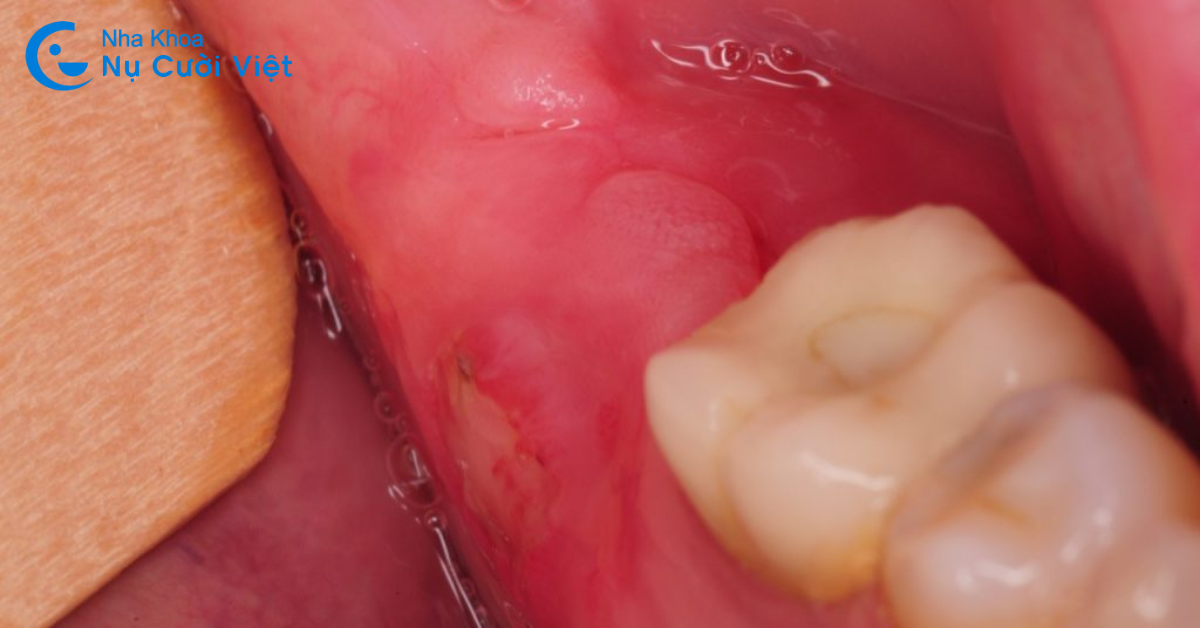

Triệu chứng mọc răng khôn cũng khá phổ biến trong quá trình mọc răng khôn chính là sưng lợi. Kích thước của răng khôn khá to mà cung hàm chúng ta đã trở nên hẹp dần. Răng khôn khi mọc không đủ vị trí để mọc sẽ mọc lệch, mọc ngầm. Răng không dễ dàng trồi lên trên bề mặt được. Dẫn đến hiện tượng nướu (lợi) sưng đỏ. Kéo theo việc này sẽ là đau nhức kéo dài và trầm trọng hơn nếu không được xử lí.

Việc sưng lợi khi mọc răng khôn ngoài việc đau nhức còn gây nên những bất tiện khác. Tiêu biểu là cản trở việc ăn nhai, dễ cắn vào má khi ăn uống hoặc nói chuyện.

2.6. Triệu chứng mọc răng khôn: Xuất hiện mủ và hơi thở có mùi

Triệu chứng mọc răng khôn khá nặng đó là tình trạng xuất hiện mủ, bốc mùi và chảy máu. Bạn cần chú ý, khi xuất hiện triệu chứng này thì cần đến ngay các cơ sở nha khoa uy tín để tiến hành kiểm tra. Việc trì trệ sẽ khiến tình trạng diễn biến nặng hơn. Cũng là nguy cơ tiềm ẩn hình thành các bệnh lí răng miệng nghiêm trọng khác.

Khi xuất hiện triệu chứng mọc răng khôn này thì tuyệt đối không tùy tiện mua thuốc giảm đau hay chống viêm gì ở nhà thuốc. Bạn cần có sự thăm khám cẩn thận của bác sĩ chuyên khoa và có hướng xử lí phù hợp.